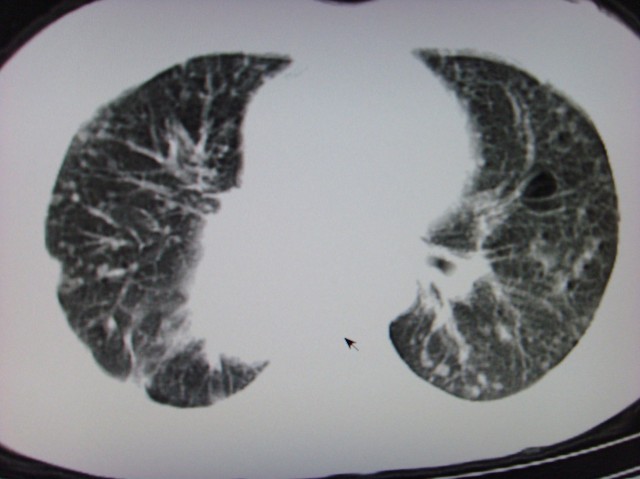

典型 中央型ca伴双肺、淋巴结、胸膜转移

支持楼主的中央型肺癌,肺内,纵隔内淋巴结转移

支持楼主诊断:中央型肺癌,肺内,纵隔内淋巴结转移。